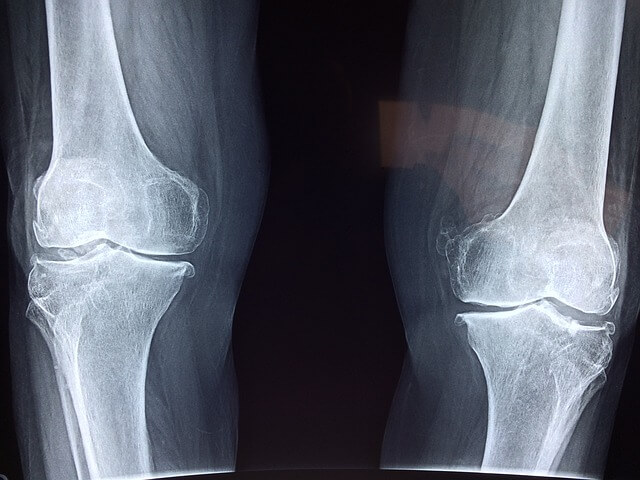

시서스는 특히 관절 및 연골 건강에 도움이 되는 것으로 알려져 있습니다. 일부 연구에 따르면, 사각 말린드나무는 관절염 및 골다공증과 같은 자주 발생하는 섬유염 관절 질환에서 두통, 염증 및 아픔 완화 도움을 줄 수 있습니다.